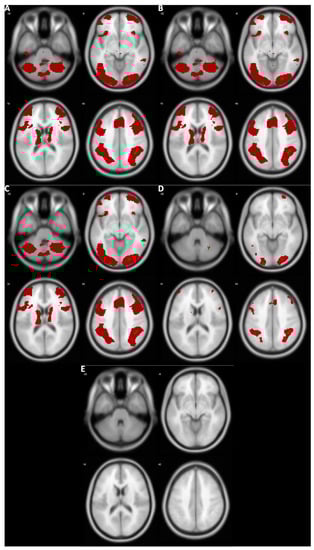

3.1. Voxelwise Second-Level fMRI Analyses